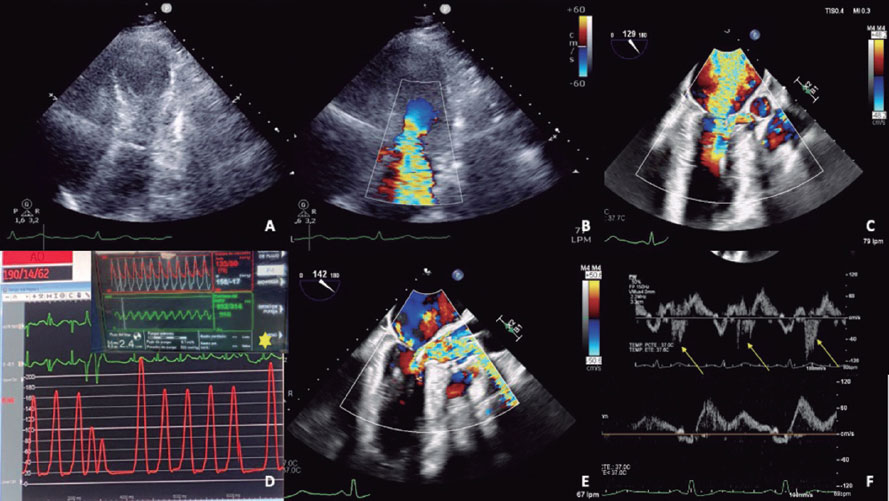

El implante del dispositivo Imp ella-CP (figura 1D, asterisco) ajustando un flujo de 2,4 l/min (P4) para evitar la succión, produjo una mejora hemodinámica y respiratoria inmediata, con disminución de la insuficiencia mitral (figura 1E,F, flechas: onda S sistólica). Una segunda rama septal (RS) mostraba compresión extrínseca, y se seleccionó tras confirmar la irrigación septal (figura 2A, flecha: segunda RS; asterisco: primera RS). Se implantaron 2 coils (figura 2B) por la potencial reversibilidad, con reducción inmediata del flujo y reducción de ODTSVI.

Tras 24 horas, la situación hemodinámica se deterioró. Debido a una ligera elevación de las enzimas cardiacas y una reaparición de ODTSVI, se realizó ablación con alcohol de la segunda RS. Dado que persistía la contractilidad más basal del septo (figura 2C, óvalo), se decidió ocluir también la primera RS, implantando un stent farmacoactivo en la descendente anterior proximal debido a la imposibilidad de una cateterización selectiva (figura 2D); tras ello, se observaron acinesia basal septal e insuficiencia mitral ligera (vídeo S2).